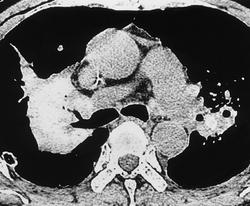

В III стадии П. узелки сливаются между собой, образуя крупные узлы или конгломераты. Между узлами можно выявить кавернозные полости, участки цирроза. В базальных отделах легких - буллезная эмфизема. Лимфатические узлы корней легких и средостения заметно увеличены, в их толще имеются включения солей кальция. В части случаев обызвествление лимфатических узлов носит краевой скорлупообразный характер. Диафрагма деформирована, фиксирована. Реберно-диафрагмальные синусы облитерированы. Сердце легочное.

"Кавитация" в результате ишемического некроза.